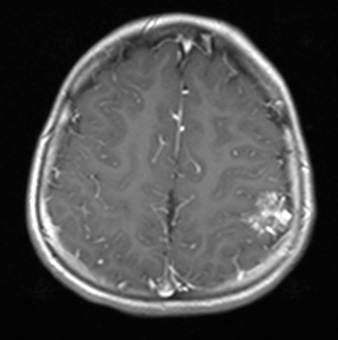

34A3,4 These T1-weighted images with administered contrast show the hyperintense vascular channels and involved parenchyma in both axial (34A3) and coronal (34A4) views.